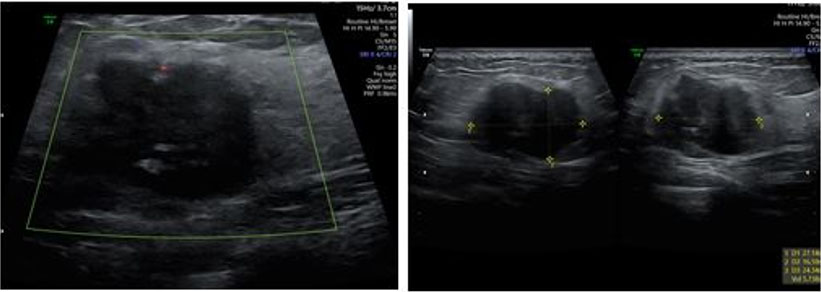

A 29-year-old woman, who had lumpectomy in 2016 which was found to be benign, visited for preconception counseling. Unfortunately, she had not retained the medical notes and discharge summary of that surgery. She again presented with a lump in the same breast and was recommended to have an ultrasound which showed BIRADS 4–5 suspicious of malignancy (Figure 1). Mammography picked up a 3 × 2.3 cm mass in upper-inner quadrant (UIQ) of left breast with left axillary lymphadenopathy. She was referred to a breast oncologic surgeon who recommended a biopsy. The mass was diagnosed as invasive ductal carcinoma (IDC) grade 3, ki-67>25% and a positron emission tomography (PET) scan was recommended. During this period, she missed her periods and tested positive for pregnancy and hence PET scan was deferred. She was offered termination, but she declined. She underwent left breast conservation surgery with axillary sampling and clearance. She was diagnosed as stage IDC III p T2N2Mo, HPR T 3 cm IDC IIILVI +9/22 nodes positive. The patient underwent chemotherapy with Doxorubicin and Cyclophosphamide from second trimester three weekly for 4 cycles. Her anomaly scan was normal, but she had complete placenta previa due to which she had repeated episodes of bleeding per vaginum. This required multiple admissions to the hospital to try and prolong the pregnancy. Her antenatal growth scans were done regularly to assess the growth of fetus and look for any lesions (metastasis) in liver.

Figure 1: Ultrasound images of the breast lump.

Ultrasound remains the first line imaging modality for diagnosing PABC as it has high sensitivity. Pregnancy-associated breast cancer appears as a hypoechoic mass with fluid in center due to cystic degeneration of central tissue accompanied by irregular margins and posterior shadowing. Ultrasound also helps diagnose nodal disease and response to chemotherapy. Mammography can be done with Mediolateral Oblique View. The combination of ultrasound and mammography has diagnostic efficacy comparable to contrast-enhanced breast magnetic resonance imaging (MRI). Contrast-enhanced MRI is restricted in pregnancy as Gadolinium based contrast agents cross the placenta to reach the baby. It stays in amniotic fluid where its ions can affect the baby [3]. A fine needle aspiration biopsy or core biopsy can help with the diagnosis. In our case Mammography had already been done by the time she realized she was pregnant, and confirmation was done by a biopsy.